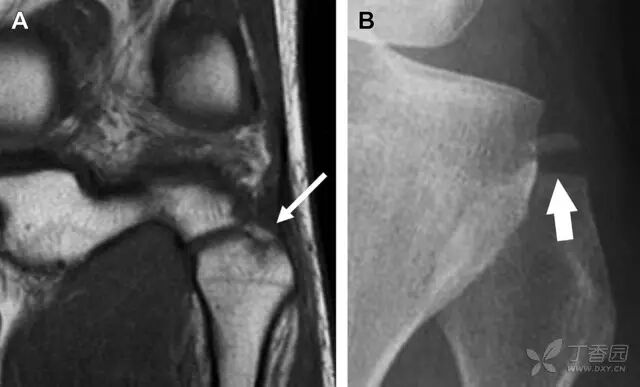

图 5 距骨后突骨折。侧位片(A)和 MRI 矢状位 T1 加权像(B)均示后外侧突的简单骨折(箭头),再次阅片时才发现 X 线片上的骨折;侧位片(C)和 CT 横断面图像示后内侧突的粉碎型骨折(箭头)

月骨周围脱位和月骨周围骨折脱位常发生于摔倒后手掌撑地,由过伸、轴向暴力所致。所谓的「脆弱区」包括桡骨茎突、大多角骨、舟状骨、头状骨近端、钩状骨近端、三角骨的月骨缘、尺骨茎突。

图 7 经舟状骨骨折月骨周围脱位(腕关节前后位、斜位、侧位)。(A,B)前后位、斜位示月骨腰部骨折(黑箭头),第 1、2 腕弧中断,舟状骨近极(*)仍在原位,而远极(虚线)背侧脱位